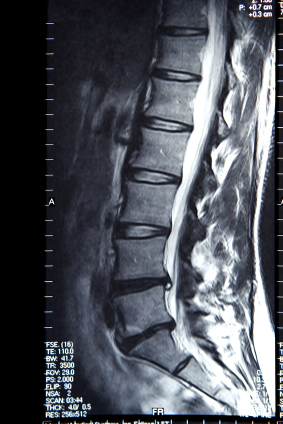

Изучение истории болезни и медицинский осмотр не проводятся. МРТ или КТ Миелограмма необходимо для установления диагноза.

Медицинские процедуры, проводимые при заболевании межпозвонковая грыжа: Магнитно-резонансная томографияЛЕЧЕНИЕ И ПРОФИЛАКТИКА